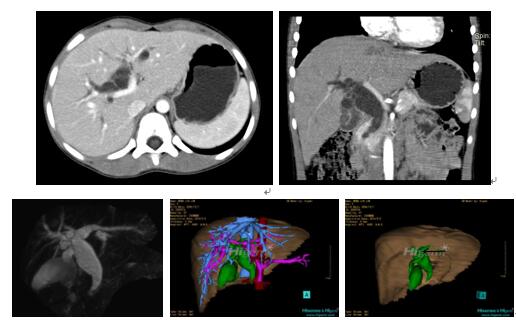

7、CT检查

可明确胆总管扩张的程度、位置,胆总管远端狭窄的程度以及有无肝内胆管扩张,扩张的形态及部位等,有助于术式的选择。近年来由于螺旋CT及其三维甚至四维成像技术的发展,可以立体性地全面地反映肝内胆管的影像。(图29-7)

图7:CT 所示的先天性胆管扩张症的肝内胆管扩张

(1)平面CT所示的先天性胆管扩张症的肝内胆管扩张

(2)CT三维成像所示先天性胆管扩张症的肝内胆管扩张。

8、核磁共振及核磁共振胰胆管成像技术(MRCP)

是90年代才成熟应用到临床的一种高新无创成像技术。利用核磁共振的特殊呈像技术获得清晰的胰胆管呈像效果,甚至可明确地判断出是否合并胰胆合流异常。近年大量临床研究表明,单纯的胆管扩张症的 诊断远不能适应正确指导手术。(图8)

图8:先天性胆管扩张症的MRI, MRCP检查

(1)(2)平面MRI所示的先天性胆管扩张症肝内胆管的扩张

(3) MRCP检查所示的先天性胆管扩张症合并胰胆管合流异常。

图10:先天性胆管扩张症囊肿型三维重建虚拟肝脏、胆道显像

a 图为术前二维CT扫描图像,箭头所示为肝内胆管扩张;b 图为CT经多平面重组技术(MPR)图像后处理所得的重建图像,可显示胆总管明显扩张合并肝内胆管扩张;c 图为MRCP显示胆总管呈囊柱状扩张,直径>1 0 cm,伴肝内胆管扩张;d 图示Hisense CAS三维重建清晰显示肝脏、胆道系统及其与门静脉、肝动脉、肝静脉等之间的空间解剖关系;e 图示Hisense CAS可从任意角度以不同脏器组合显示,明确胆道系统与其伴行的门静脉系统的空间解剖关系;f 图示胆道系统立体形态及与肝脏整体的空间关系,箭头处显示肝内胆管狭窄部位发生于左右肝管汇入肝总管处。术前规划需行肝内胆管扩大成形术。